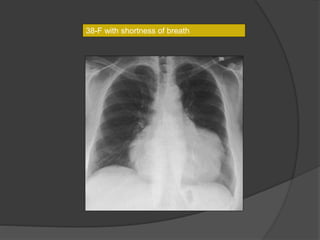

38-F with shortness of breath

Pericardial Hydatid

 Rare -may be mistaken for tubercular pericarditis

 Non specific symptoms

 Imaging

CT- cystic nature, daughter cysts & membranes

- pericardial effusion +/-

MR- highly specific

- characteristic T2 hypointense wall of the cyst

Singhal M et al. Isolated pericardial hydatid cyst.

Postgraduate Medical Journal 2011; 87: 790.